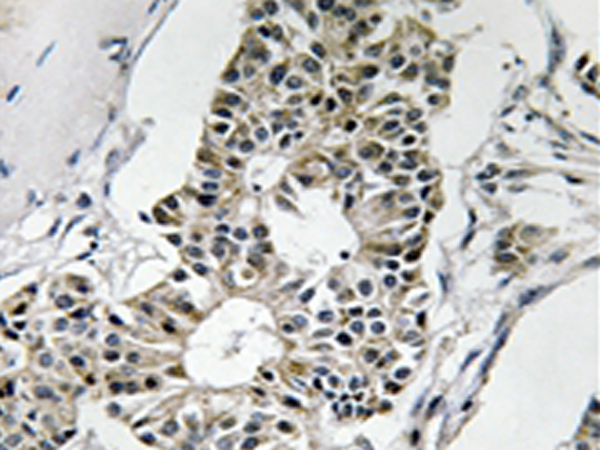

IHC positive control:

Human breast carcinoma tissue

IHC Recommend dilution:

50-100